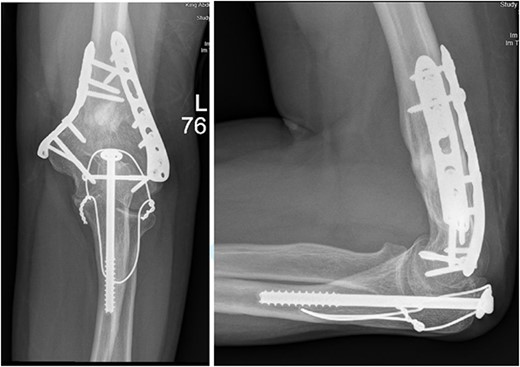

After surgery, the patient was taken back to the ICU and was followed daily by the upper limb orthopedic surgery team for wound care and change of dressings. Four days later, the patient’s condition had improved and he was assessed for distal neurovascular function, which was intact. Afterwards, range of motion was assessed, and no complications were reported before discharge. The patient was kept as an inpatient for almost two more months under the orthopedic trauma team for continuation of management and patient optimization. After discharge, the patient was followed in the orthopedics upper limb and trauma clinic for almost 3 years (Figs 4– 6).

(A). Late follow-up anteroposterior (AP) view of the left elbow after ORIF. (B) Late follow-up lateral view of the left elbow after ORIF.

Our patient was followed afterwards for three years with serial x-rays. No signs of growth arrest or deformity due to our surgical intervention were noted. Instead, on follow up, our patient had a functional range of motion. Elbow range of motion was documented to be 30° extension to almost full flexion and intact pronation and supination. The range of shoulder motion was documented as full. Good healing was observed, but there was some hardware prominence that slightly affected the range of motion, and the patient will be booked for hardware removal. The patient was happy and satisfied about the overall outcome and restored functionality.